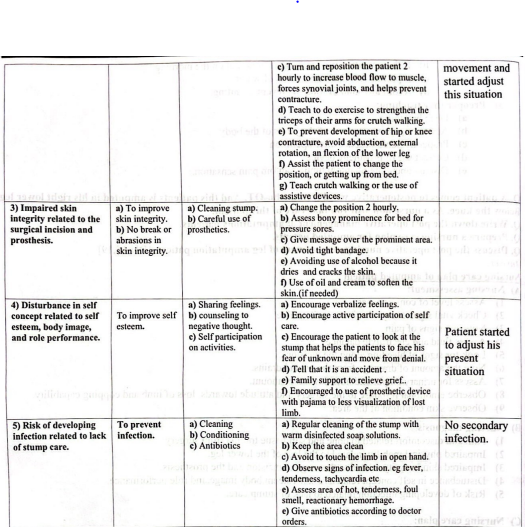

B) Nursing diagnosis:

1) Pain and discomfort related to bone and soft tissue trauma from surgery.

2) Impaired physical mobility related to the loss of the lower leg.

3) Impaired skin integrity related to the surgical incision and the prosthesis. 4) Distuebance in self concept related to self-esteem, body image, and role performance.

5) Risk of developing infection related to lack of stump care.

C) Nursing care plan: